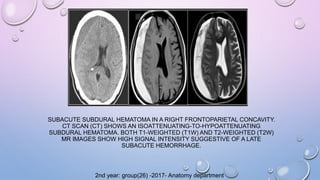

SUBACUTE SUBDURAL HEMATOMA IN A RIGHT FRONTOPARIETAL CONCAVITY.

CT SCAN (CT) SHOWS AN ISOATTENUATING-TO-HYPOATTENUATING

SUBDURAL HEMATOMA. BOTH T1-WEIGHTED (T1W) AND T2-WEIGHTED (T2W)

MR IMAGES SHOW HIGH SIGNAL INTENSITY SUGGESTIVE OF A LATE

SUBACUTE HEMORRHAGE.